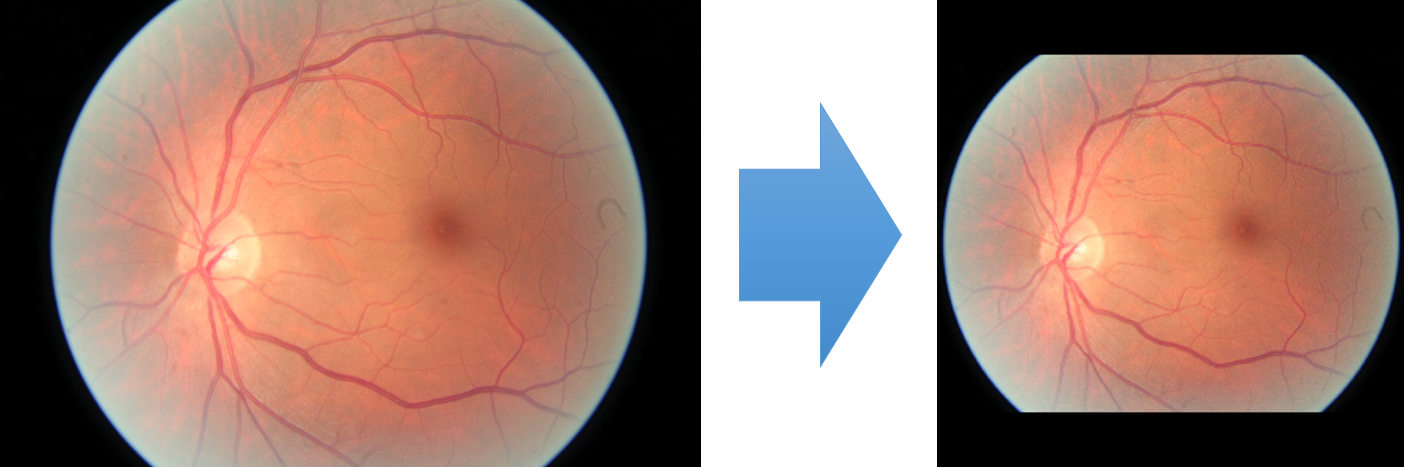

To model how different classifiers will respond to a given input , we assume that the prediction from classifier is sampled from a beta distribution that is characterized by two parameters by and . We further assume that is fixed to the same constant value for all ’s. Under this assumption, each input can be described by ( can be calculated since is fixed), easing further analysis. The Severity Level (SL) of the case represented by image can be characterized by the parameter . The larger the value of , the more severe the case of is. When and are close, the case is ambiguous as the distribution shifts towards being symmetric (i.e. signifying much disagreement among classifiers) rather than being one-sided (i.e. consensus among classifiers that is negative or positive). We provide a set of examples in Figure 2 and also Figure S.8 in the supplementary materials showing how the beta distribution can be used to capture diverse predictions given by an ensemble learner.

We conducted a case study on diagnosing diabetic retinopathy with ensembles of DL models. For benchmarking the performance of our ensemble-based solutions under the scheme described in Sec.3.3, we used two popular collections of diabetic retinopathy image data, the Kaggle Diabetic Retinopathy dataset [22] (hereafter referred to as “Kaggle-DR”) and the Messidor-2 dataset [23], each respectively consisting of and high resolution images. Diabetic retinopathy is graded into five SLs, as displayed in Figure 2. Following the problem setup used in previous papers [24], we trained models to distinguish the referable (SL2-4) cases from the non-referable ones (SL0 & SL1) (see Section B.1 for more detailed descriptions). We also tested our trained ensemble models on two o.o.d. image datasets (ImageNet [25] and CIFAR-10 [26]) to examine their capabilities of identifying o.o.d. inputs (see Section B in the supplementary materials).

The Kaggle-DR dataset comprises high resolution images. The presence of diabetic retinopathy is rated into five different SLs: no-DR (SL0), mild (SL1), moderate (SL2), severe (SL3), and proliferate (SL4), as illustrated in Figure 2. We divided the Kaggle-DR dataset into a development set and a test set, which respectively consisted of and images. The data in the development set were used to train and validate our Deep Learning (DL) models. The Messidor-2 dataset [38] that consisted of images was also used in our experiment as an additional dataset to test the true generalization performance of the models trained on the Kaggle-DR dataset. Images in Messidor-2 dataset were graded into the five SLs as in the Kaggle-DR dataset. Figure S.1 provides an illustration of the datasets used in our experiments.

The image data used in our experiment were all unified into square-shaped images with resolutions or in our preprocessing procedures. For training each neural network model, only images of the same resolution were used. The original images came with either of the two forms as exemplified in Figure S.2. In the first form (Figure 2(a)), the entire fundus was visible in the image. We cropped the image such that the fundus was tightly fitted inside the square. In the second form of input images shown in Figure 2(b), part of the fundus was not visible. We padded blank strips to make the image square-shaped and in a unified resolution. See the provided code for further details.